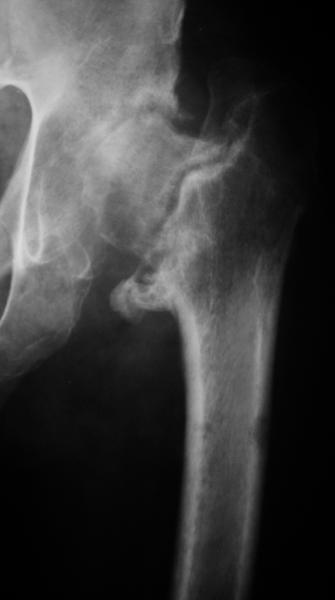

AV> опираясь на стул. На ногу не наступает. Укорочение 8 см. Иногда

А за счет чего такое укорочение? По снимку не видно соответствующего дефекта. Ну плюс приводящая контрактура - но все равно как-то уж больно много. Может, сделать снимки и таза обзорный с обоими проксимальными отделами бедра, и коенный суставов с приложенной линейкой какой?

Судя по снимку, максимум истинное укорочение около 4 см, что может быть коррегировано интраоперационно. Вопрос в другом: куда ставить ацетабулярный компонент в истинную или во вновь сформированную ( впадина диспластичная).

Терзают смутные сомнения, что у больного и до перелома нога уже была короче: порасспрашивайте анамнез поподробнее.

Невозможно не согласиться с Анатолием, чтобы заниматься адекватным планированием как минимум прямая проекция таза должна быть сделана, как

максимум для оценки состояния мышц( насколько реально возможно низвести бедро) прямая проекция таза с тракцией за больную ногу.

The X ray that you provided does not show 8 cm of shortening. Perhaps you could send one showing the whole pelvis and proximal femurs.

До травмы проблем с ногой не было. Укорочения, болей и т.п. не отмечал. Сегодня перемерял укорочение - меньше 7 см намерять не

получается :)

По уровню малых вертелов (с учетом рентгеновского увеличения) получается 5 см. Клинически ногу низвести путем тракции невозможно. Из движений - сгибание до 40*, остальные движения "символические".

Ортопедическое укорочение пострадавшей ноги может быть и 7, и 10 см. за счет контрактур в тазобедренном суставе, а вот истинное укорочение, судя по представленным рентгенограммам, вряд ли больше 4 см.